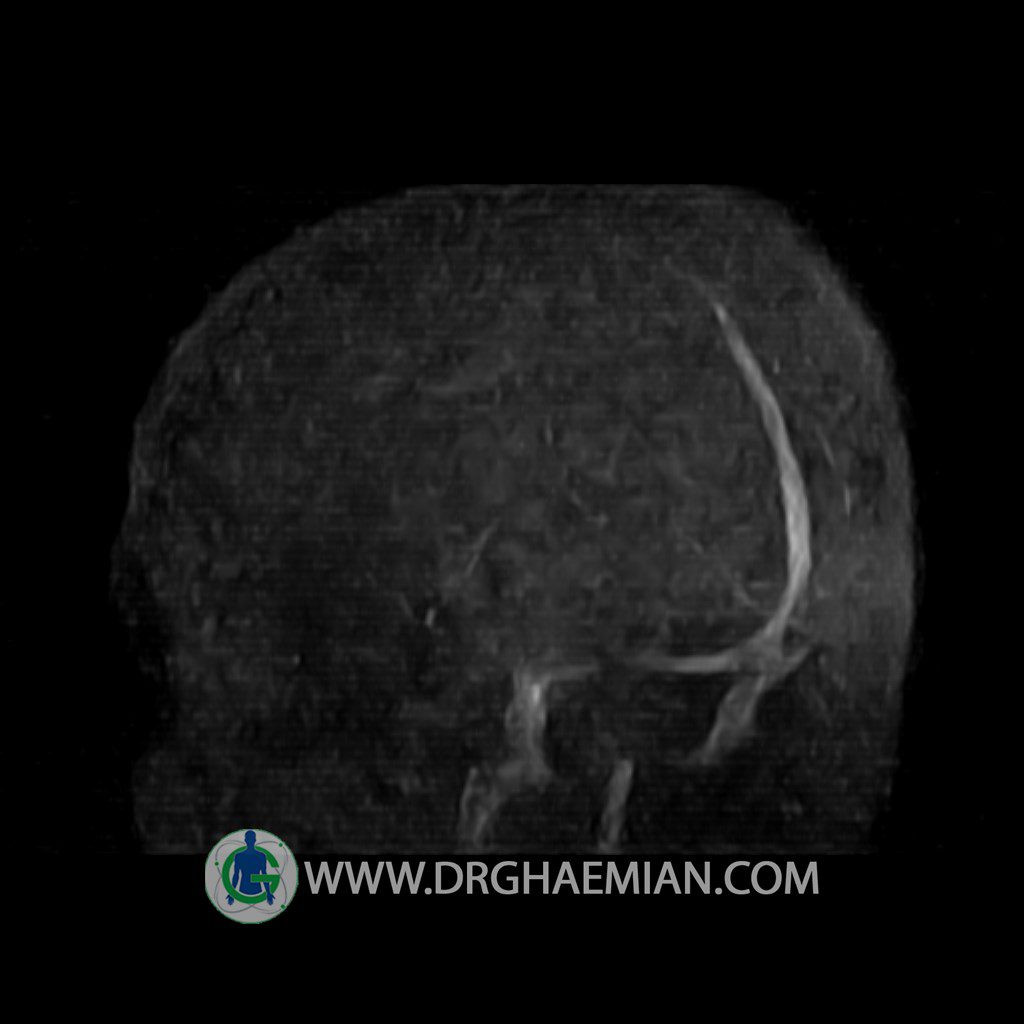

ام آر وی یک روش تصویربرداری دقیق و غیر تهاجمی است که برای معاینه ورید های بدن و ارزیابی سلامت رگ ها استفاده می شود. ورید ها خون را از اعضای بدن به قلب باز می گرداند تا دوباره اکسیژن و مواد مغذی به خون داده شود. ام آر وی جریان خون را ارزیابی و موارد غیرعادی مضر مانند لخته های خونی را شناسایی می کند. در این کیس ترومبوز دیواری مغز در سینوس عرضی راست و ترمبوز جزئی در سینوس عرضی چپ دیده می شود.

Technique: TOF ( time of flight ).

Images of the venous cranial vessels demonstrates a superior sagittal sinus of normal caliber with normal arrangement of draining superficial cerebral veins.

– Narrowing of left transverse sinus with filling defect & inthimal irregularity

suggestive for partial thrombosis

– Inthimal irregularity in anterior wall of right transverse sinus suggestive for mural thrombosis

are seen